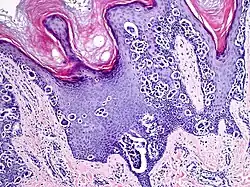

An acral nevus is a cutaneous condition of the palms, soles, fingers, or toes (peripheral body parts), characterized by a skin lesion that is usually macular or only slightly elevated, and may display a uniform brown or dark brown color, often with linear striations.[1]: 1726